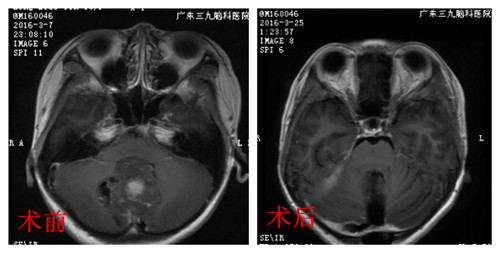

影像学资料显示,婷婷是后颅窝占位性病变,考虑髓母细胞瘤的可能性大,应尽快手术治疗,解除这个肿瘤对婷婷生命造成的危害。确定手术方案后,小儿神经外科在显微镜下为婷婷进行肿瘤切除手术,并完好地保护了婷婷的重要脑组织部分。术后,婷婷辅以放化疗治疗,头痛、呕吐症状消失。

术后病理报告提示:髓母细胞瘤。